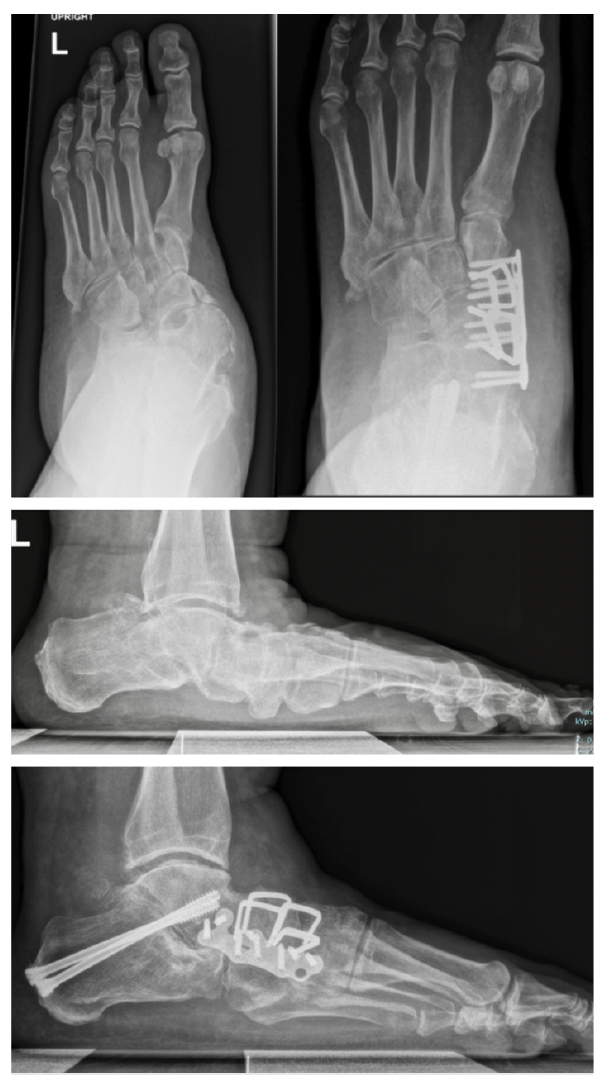

Radiographs are a critical component of the preoperative workup. AP and lateral foot and AP or mortise ankle are mandatory for surgical planning and a hindfoot alignment view is strongly recommended.9 Advances in radiographic imaging leading to the development of weight-bearing CT scanning (WBCT) have led to several paradigm shifts in the understanding of the PCFD deformity and its surgical correction.

The second principle is to correct the rearfoot deformity perpendicular to the ground. When deciding which procedure to perform, the initial distinction is between Evans/medial displacement calcaneal osteotomy (MDCO) or subtalar joint (STJ) fusion. The Evans/MDCO is for moderate, reducible deformities, whereas severe, rigid deformities are best served by STJ fusion. Clinical examination distinguishes between flexible and rigid deformities depending on the degree of reducibility. Severe, advanced deformities necessitating STJ fusion for rearfoot correction demonstrate arthritic changes at the STJ, more significant peritalar subluxation, and more severe collapse of the sagittal height of the foot on plain film radiographs.

With severe deformity with significant peritalar instability, arthrodesis procedures are required for rigid, arthritic, or severe deformities in order to reach the goal of a stable, well-positioned hindfoot.47 For rearfoot correction, the procedure of choice is an STJ fusion. Previous schools of thought have encouraged valgus positioning of the heel during STJ fusion. However, the data actually reveals that the optimal position of the rearfoot is 0–5º of varus on hindfoot alignment view, which equates to a clinically neutral heel.48

The final principle to follow when correcting PCFD is to correct the forefoot parallel to the rearfoot in the coronal plane. Restoration of the medial column is essential for long-term stability of the foot.49 It is often not sufficient to simply correct the rearfoot as there is often a forefoot supinatus element involved, which one can evaluate clinically by loading the foot and comparing the planes of the rear and forefoot.49 The Cotton osteotomy addresses any remaining flexible forefoot supinatus originating from the medial arch. Surgeons can use the Cotton osteotomy with varying graft sizes for deformity-specific correction, but the correction is directly related to the graft size. Research has demonstrated each millimeter of graft to correct the cuneiform articulation angle by 2.1º.50 Graft sizes usually range from 5–11mm.50

A Cotton osteotomy may not always be sufficient. Upwards of 50% of isolated Cotton osteotomies lose correction over time. This loss of correction results from increased motion in the medial column joints.1 If any of the joints of the medial column, including the talonavicular (TNJ), naviculocuneiform (NCJ), or first metatarsal cuneiform joint (first MCJ), exhibit any instability or arthritic changes, they should be fused.49 Considering the loss of correction observed with the Cotton osteotomy and the high prevalence of instability of the first MCJ, the LapiCotton—or Cotton combined with Lapidus—has been popularized to offset these shortcomings. The Lapidus procedure can result in shortening and dorsiflexion of the first ray, but the plantarflexory and grafting components of the LapiCotton provide a powerful combination to reestablish the foot tripod.52 Post-Lapidus, the function of the peroneus longus remains intact; medial column eversion increases at the NCJ if the first ray is not shortened or elevated. The net effect is increased efficiency in stabilizing and locking the first ray.53 This allows realignment of the plantar fascia and facilitates the proper functioning of the windlass mechanism.42